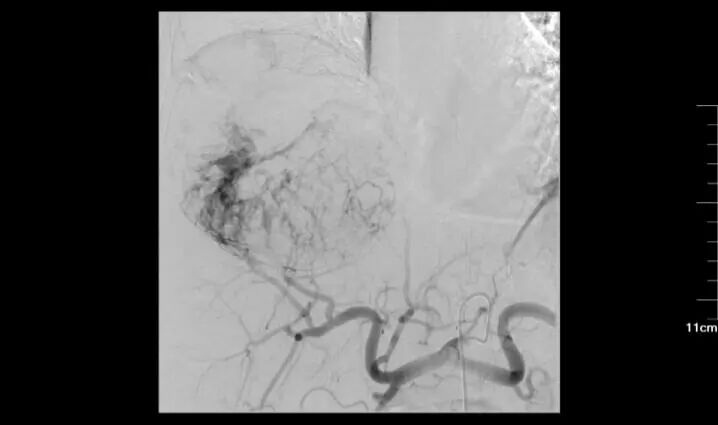

73歲男性,巨塊型肝癌,失去手術(shù)機(jī)會(huì),多次介入治療并聯(lián)合靶向治療,長(zhǎng)期帶瘤生存。